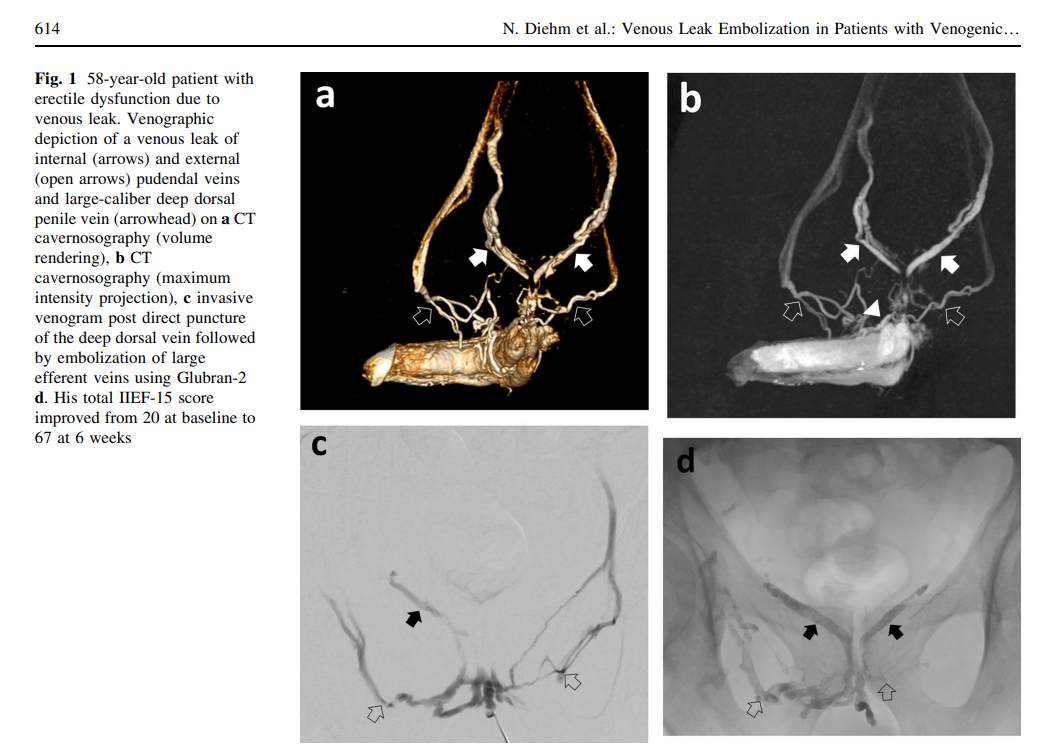

Эректильная дисфункция — это не просто медицинская проблема, это состояние, которое может значительно повлиять на интимную жизнь и уверенность Вашего мужчины. Одной из причин, вызывающих эту проблему, является венозная утечка, когда кровь не задерживается в пенисе из-за недостаточного давления в венах, отвечающих за эрекцию.

Это приводит к мягким, кратковременным эрекциям, которые не удовлетворяют ни вас, ни вашего партнера. Но есть решение — комплексная диагностика и лечение, включая современную методику эмболизации венозной утечки. Комплексный подход и помощь консилиума врачей поможет вернуть нормальную эректильную функцию Вашему мужчине.

Исследования показывают, что процедура значительно улучшает эректильную функцию и качество жизни мужчин.

Например, в одном из исследований, проведенном в 2012 году, лечение оказалось успешным для 93% пациентов, а 88,8% из них сообщили об улучшении эрекции на протяжении всего периода наблюдений. В 2014 году почти все пациенты отметили немедленное улучшение состояния после процедуры. Мета-анализ 2019 года показал, что в 86-97% случаев процедура была технически успешной, и пациенты сообщили о значительном улучшении эрекции. Осложнения были редкими и незначительными.